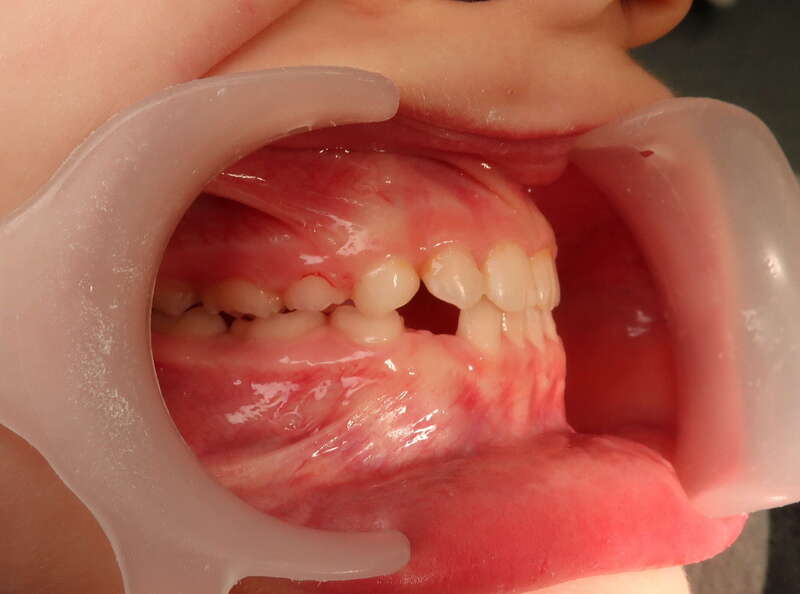

Cas n°3 traité par aligneurs (interception) - enfant

Intervenir dès 8 ans avec cette approche offre des bénéfices structurels :

• Symétrie Faciale : En éliminant le glissement de la mâchoire, on assure que le visage se développe de manière droite et harmonieuse.

• Confort Articulaire : Le recentrage prévient les tensions et les pathologies futures des articulations de la mâchoire (douleurs, craquements).

• Expérience Positive : L'absence de douleur et la simplicité des aligneurs favorisent une excellente acceptation du traitement par l'enfant.

• Simplification du futur : "Remettre la croissance sur les rails" permet souvent d'éviter des traitements beaucoup plus complexes (voire chirurgicaux) à l'adolescence.